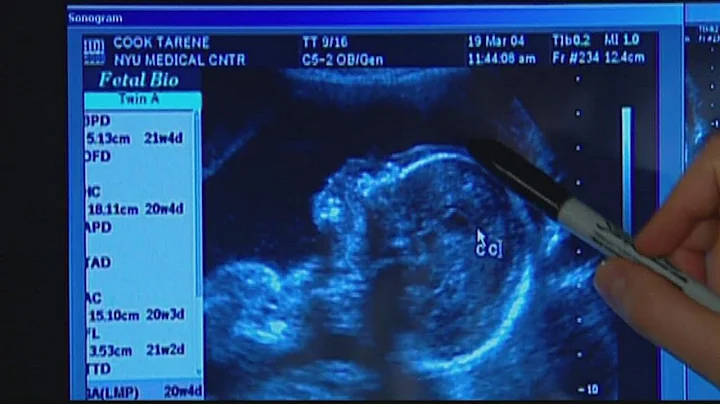

Ddc Certainty™ Non-invasive Prenatal Paternity Test

Yes, you can get a paternity test while pregnant! The Certainty™ Non-Invasive Prenatal Paternity test from DNA Diagnostics ...